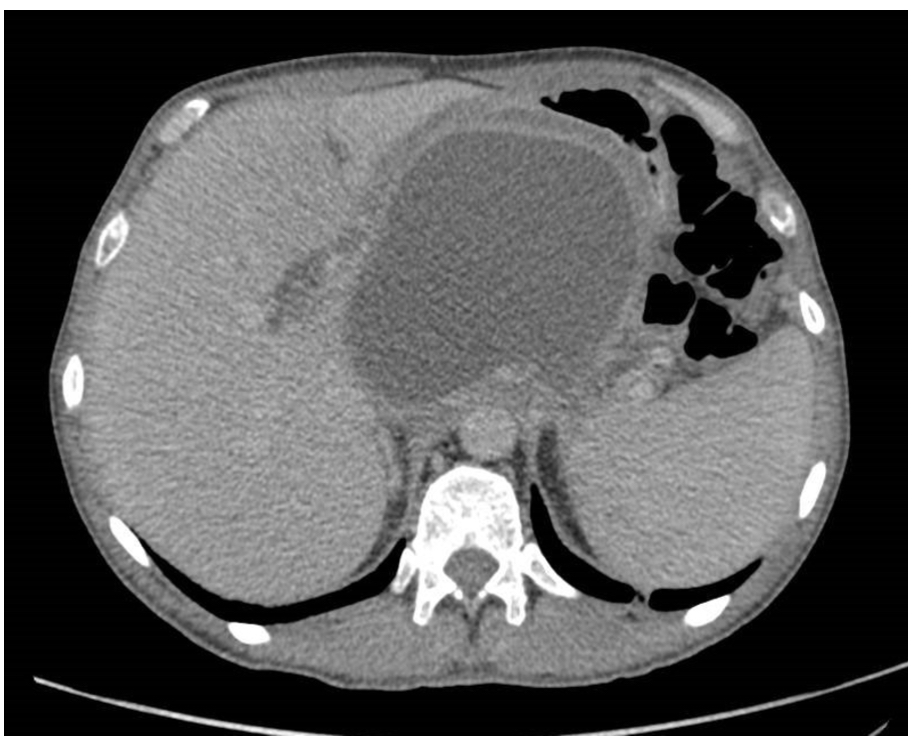

CT scan- pancreas becomes muddy *as seen on diagram *. Normally pancreas is smooth

What is pancreatic pseudocyts and when does it present

Peri-pancreatic fluid collection

increased pancreatic enzymes within a fibrous capsule. NO EPTIHELIAL LINING

it presents more than 6 weeks after pancreatitis